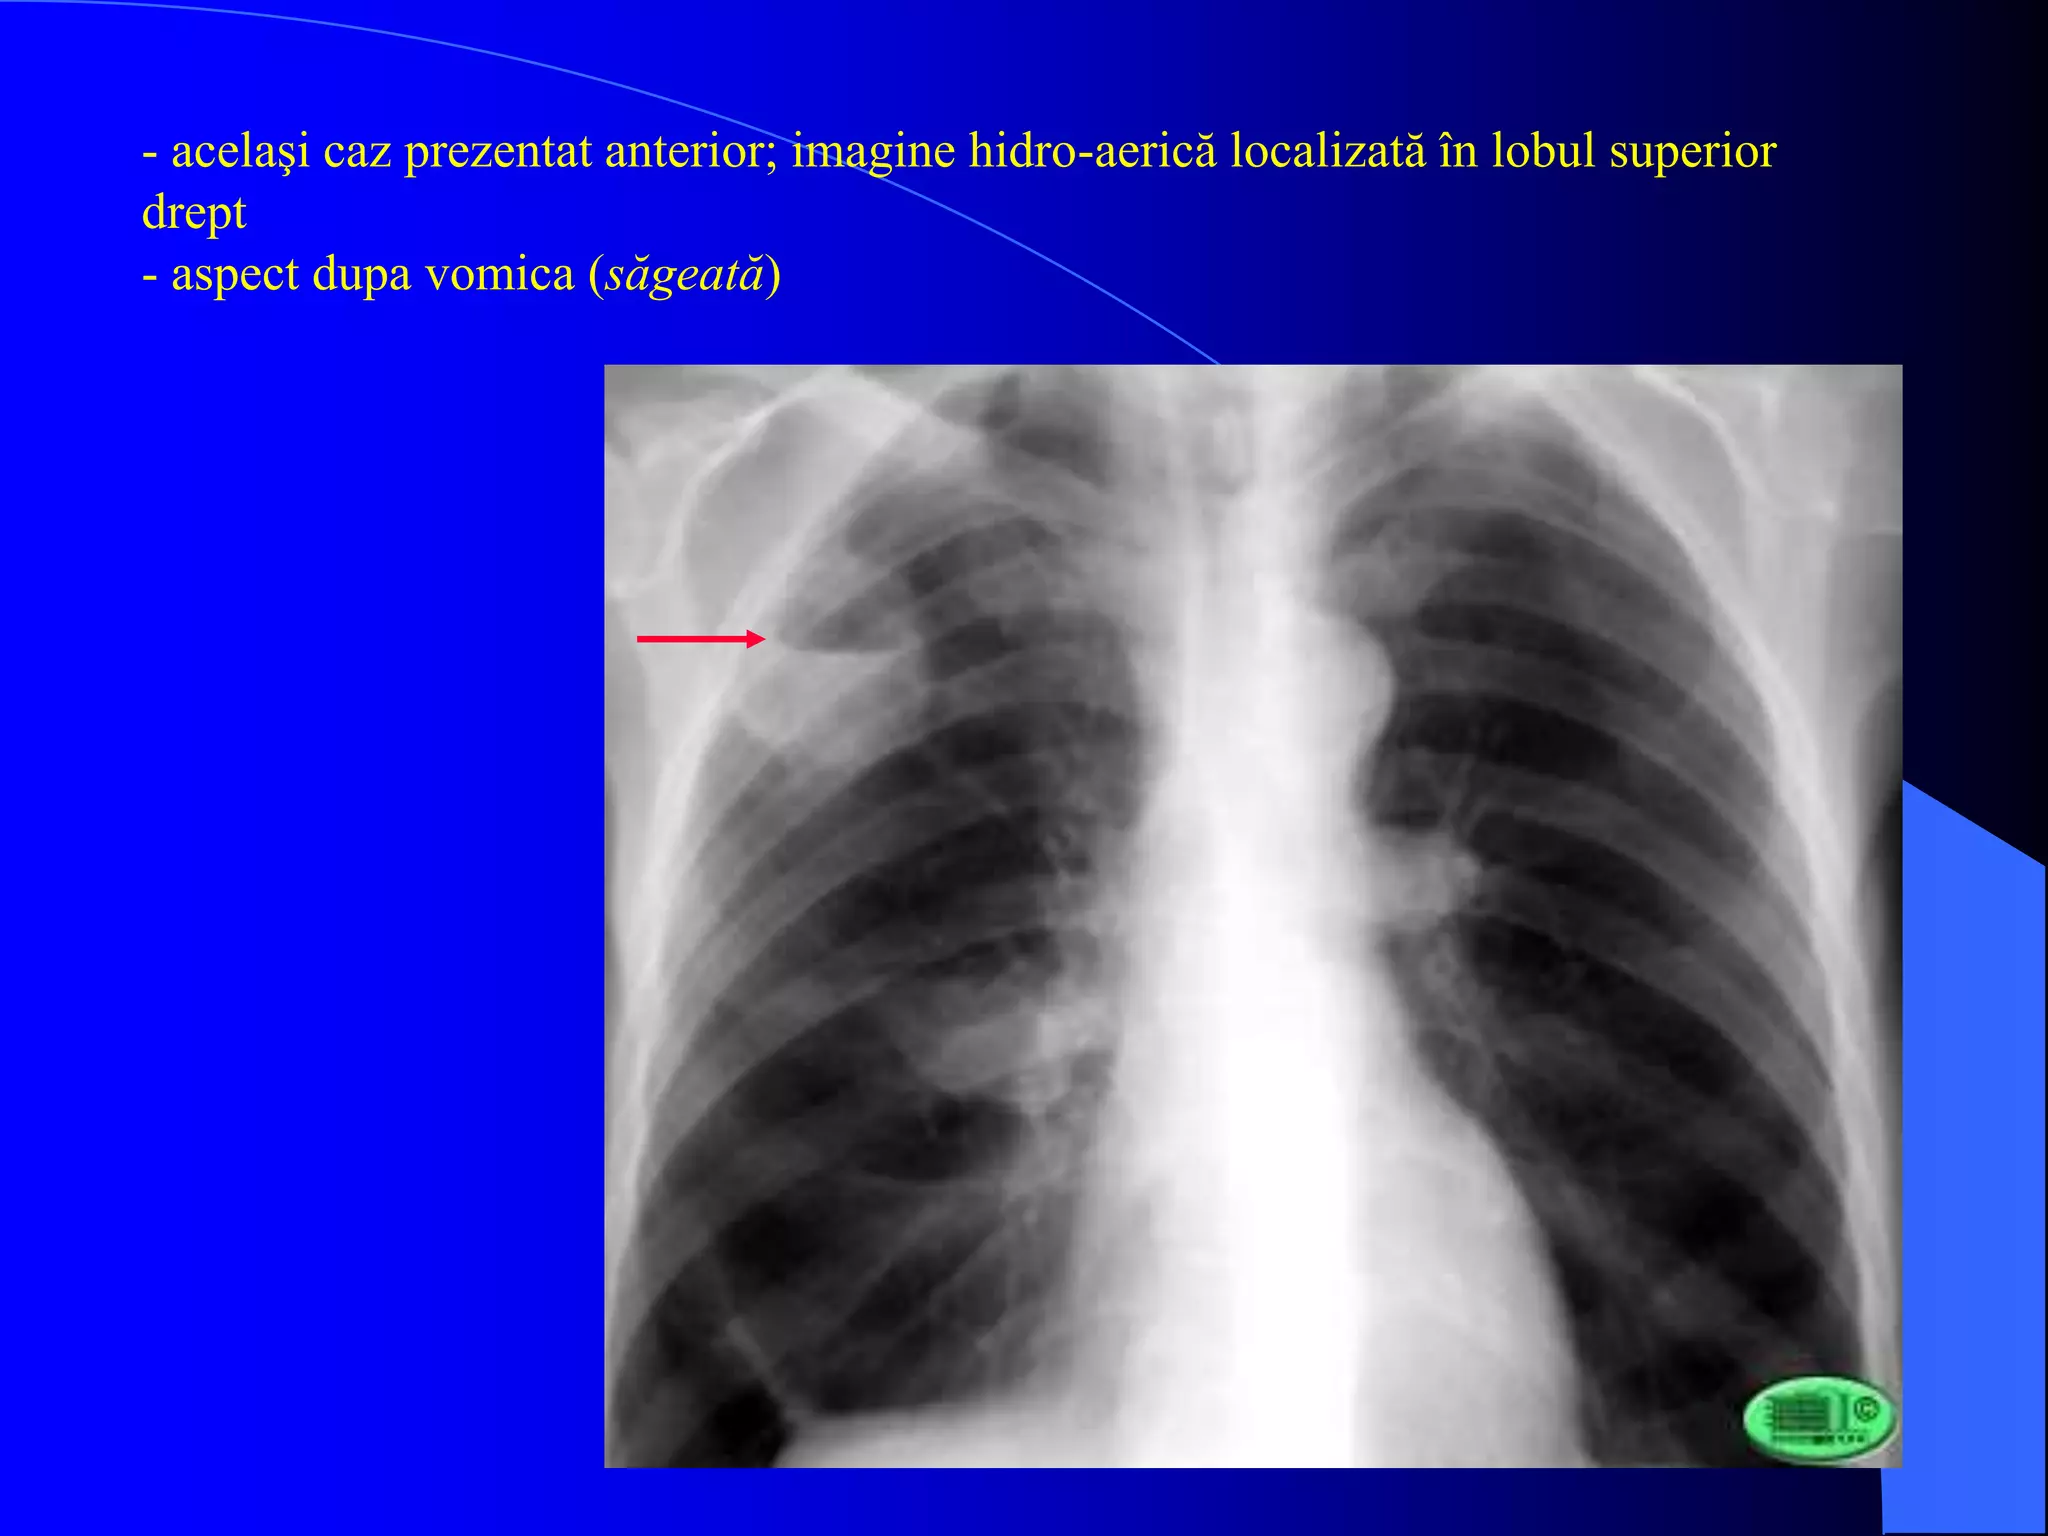

- acelaşi caz prezentat anterior; imagine hidro-aerică localizată în lobul superior

drept

- aspect dupa vomica (săgeată)